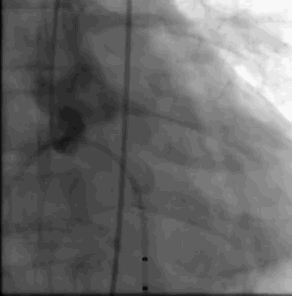

术中影像

主动脉根部造影

导丝跨瓣

选择BaIt23球囊进行预扩